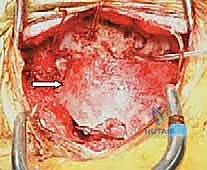

المرحلة الثالثة: الشق الجراحي والتعرض

يتم إجراء شق جراحي في منتصف الجزء الخلفي من الرقبة. يتم إبعاد العضلات برفق للوصول إلى العظم القذالي (مؤخرة الجمجمة) والفقرات العنقية العلوية.

المرحلة الرابعة: وضع البراغي وأدوات التثبيت (Instrumentation)

هذه هي الخطوة الأكثر دقة. اعتمادًا على حالة المريض، يقوم الدكتور هطيف بإحدى العمليتين:

- دمج C1-C2 (C1-C2 Fusion): يتم إدخال براغي دقيقة جدًا في الكتل الجانبية للفقرة الأولى (C1 Lateral Mass Screws)، وبراغي أخرى في عنيق الفقرة الثانية (C2 Pedicle/Pars Screws). يتم بعد ذلك توصيل هذه البراغي بقضبان معدنية صغيرة لتثبيت المفصل تمامًا.

- دمج الجمجمة بالفقرات (Occipitocervical Fusion): إذا كانت المشكلة تشمل الجمجمة، يتم تثبيت صفيحة معدنية (Plate) في العظم القذالي للجمجمة باستخدام براغي خاصة، ثم يتم توصيل هذه الصفيحة بقضبان معدنية تمتد إلى البراغي المزروعة في الفقرات العنقية (C2, C3، أو أسفل من ذلك حسب الحاجة).